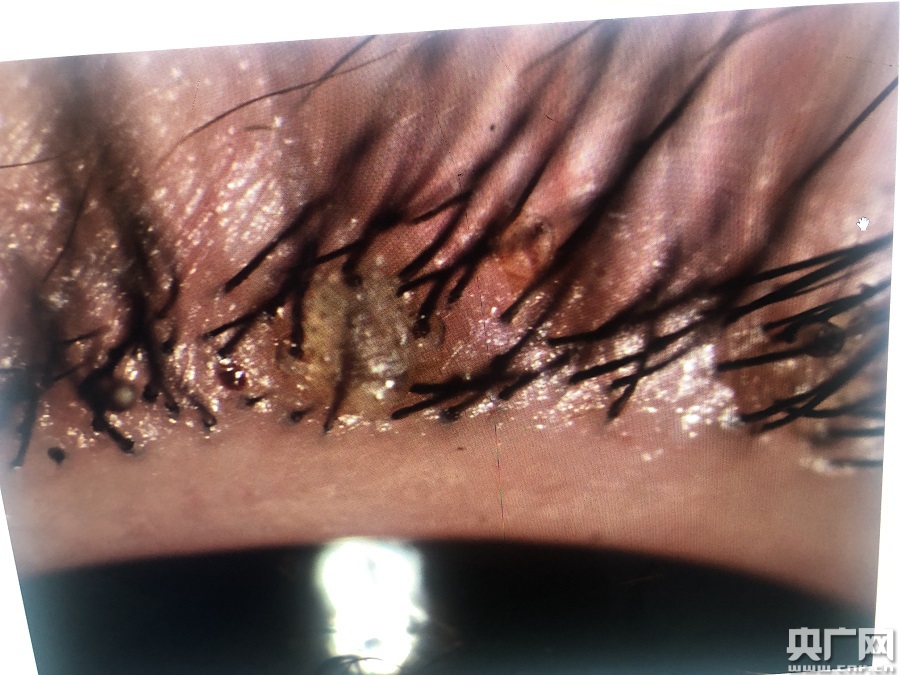

小女孩眼睫毛上長(zhǎng)滿(mǎn)陰虱(央廣網(wǎng)發(fā) 通訊員供圖)

該院眼表及角膜病專(zhuān)科副主任醫(yī)師商旭敏接診后,在裂隙燈下仔細(xì)查看,發(fā)現(xiàn)甜甜的雙眼局部紅腫明顯,睫毛根部竟然掛著幾十粒黑色未孵化的蟲(chóng)卵及白色孵化后的卵殼。仔細(xì)觀(guān)察之下,還有白色的蟲(chóng)子在蠕動(dòng)。

該院門(mén)診副護(hù)士長(zhǎng)王亞靈先在裂隙燈下夾起吸附在瞼緣上的陰虱、蟲(chóng)卵,剪去睫毛,反復(fù)確認(rèn)陰虱和蟲(chóng)卵全部除盡后,再進(jìn)行局部清洗、上藥。“經(jīng)查實(shí),這些小蟲(chóng)子是陰虱,有20多只。取出的睫毛、成蟲(chóng)還有蟲(chóng)卵都進(jìn)行統(tǒng)一焚燒。我從醫(yī)幾十年,有見(jiàn)過(guò)眼內(nèi)長(zhǎng)陰虱的,不過(guò)長(zhǎng)20多只,這還是第一次碰到。”王亞靈說(shuō)。